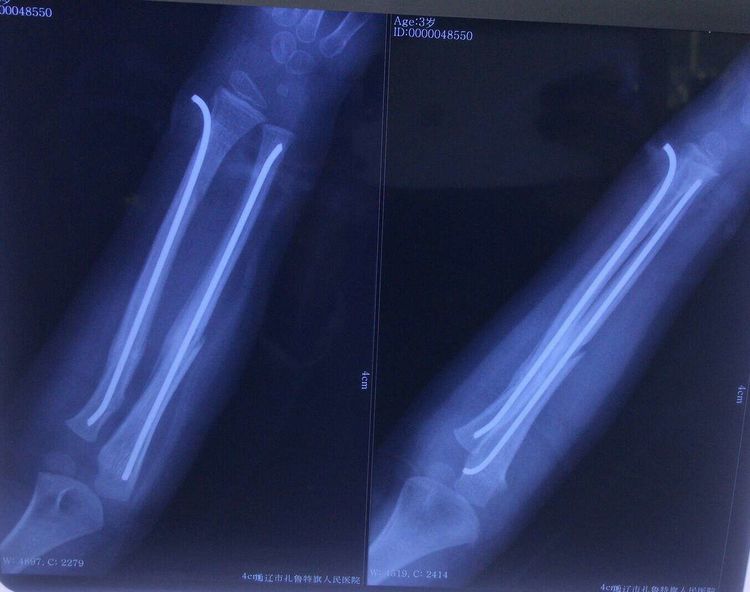

因患者年龄小,无论麻醉还是手术对患儿来说都是有一定风险和难度的,患者入院后积极完善入院检查,排除手术禁忌症,张继锋主任组织科室内进行病例讨论,决定应用克氏针模拟弹性髓内针技术,给予患儿前臂双骨折闭合复位,克氏针髓内固定手术,术前请麻醉科会诊,计划手术在全身麻醉下进行,于2020-03-09在张继锋主任和肖海祥副主任医师配合下给予患儿实施左前臂双骨折闭合复位,应用克氏针模拟弹性髓内针技术固定骨折端手术治疗,麻醉由贾雁冰主任实施,为减少全身麻醉药物剂量,减少全身麻醉并发症,也为减轻患儿术后疼痛,术中贾主任给予超声引导下腋路臂丛神经阻滞,减轻了术后患儿疼痛,增加了手术效果!

术后拍片复查,尺桡骨骨折端复位良好,内固定克氏针位置良好,均在髓腔内。